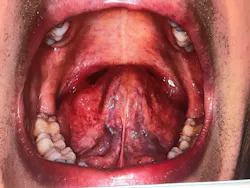

A few months ago, a dentist named Danny traveled from Sydney, Australia, to St. Petersburg, Florida, to attend one of The Dawson Academy’s courses. Danny was only in town for a few days, but he was experiencing some problems that he thought I could help solve. I agreed to see him as a patient, so we met to discuss his issues, take photographs, and complete a new-patient exam, which includes airway and medical screenings (figure 1).

Figure 1: Danny

Another dental office might have identified Danny as a classic patient with TMJ and bite issues. However, many of these symptoms—such as frequent headaches, clenching, sore jaw, and crowded teeth—are also common indicators of airway issues. Through screens for airway and breathing disorders, we were able to identify these signs and symptoms as red flags for airway issues (figures 2–4).

Figures 2 and 3: Crowding of the lower anterior teeth and scalloping of the tongue. These are common findings with airway and breathing disorders.

Figure 6: Extremely enlarged tonsillar tissue obstructing the posterior airway

Figure 7: Ankyloglossia—75% tongue-tie constriction